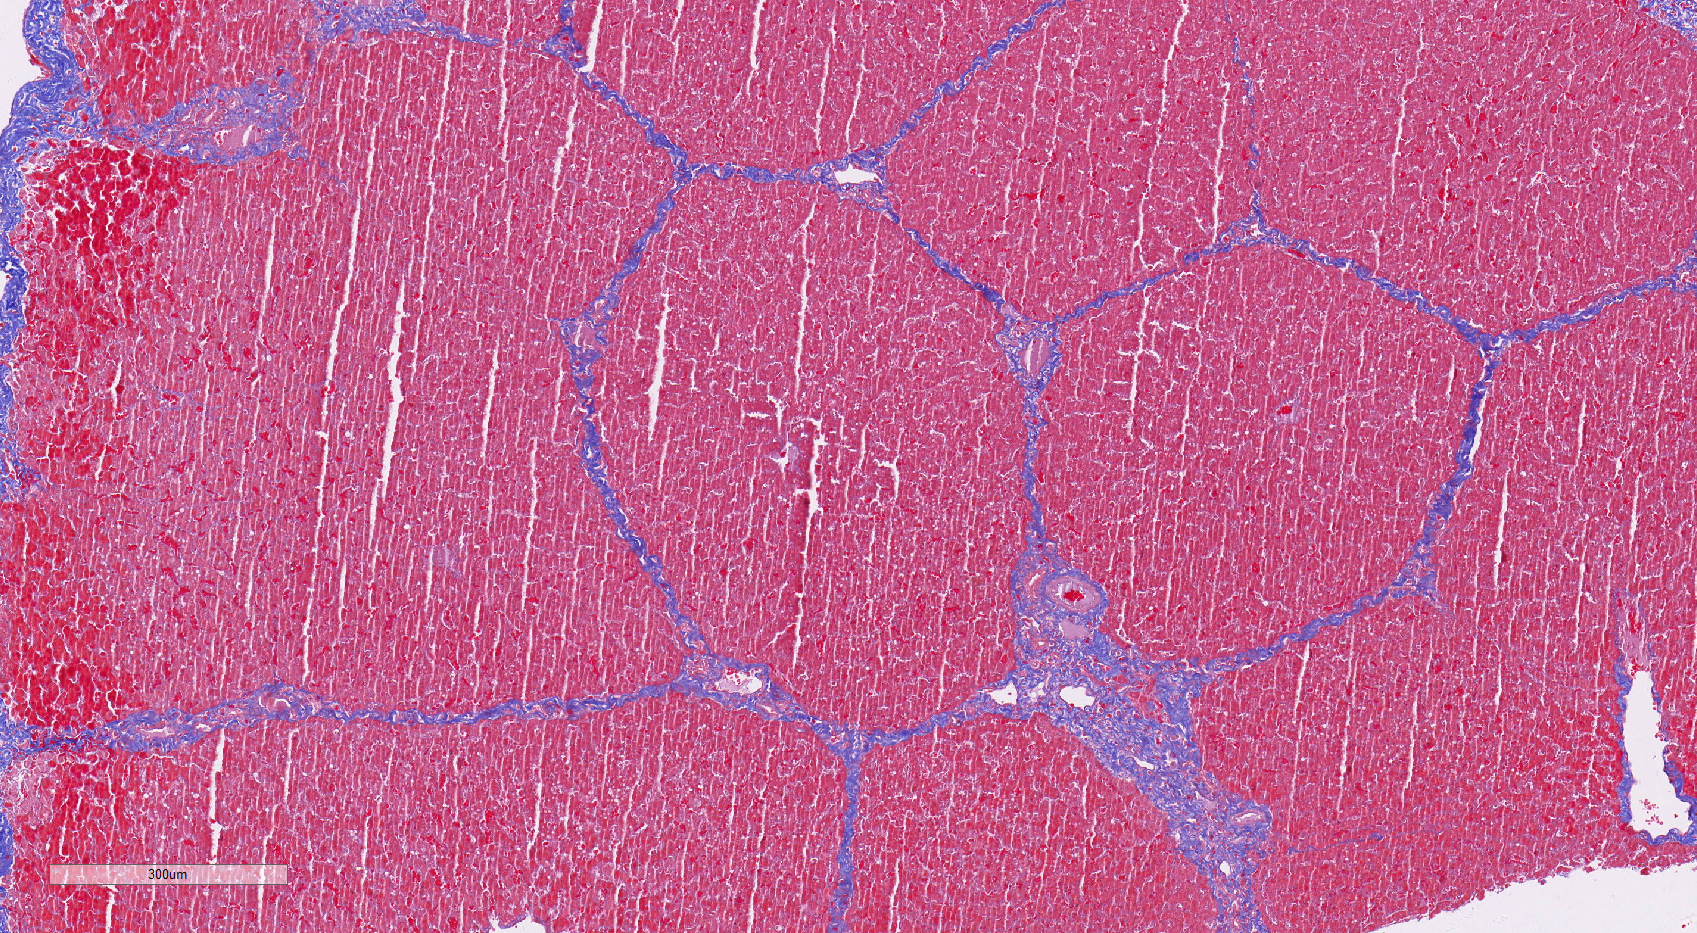

Masson染色

Masson 染色是结缔组织染色中最经典的一种方法,又称马松染色,是显示组织中纤维的主要方法之一,是胶原纤维染色权威而经典的技术方法。 Masson 染色后肌纤维呈红色,胶原纤维呈绿色或蓝色,主要用于区分胶原纤维和肌纤维。Masson 三色染色方法,是胶原纤维和肌纤维的染色方法,能够对组织和病理组织进行胶原结构的观察。

猪 肝脏 Masson染色(显 胶原纤维)